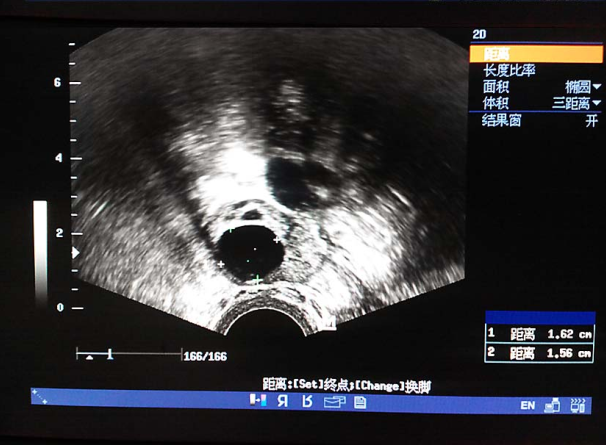

(1)超声检查:推荐使用经阴道超声,明确子宫和卵巢大小、位置、形态、有无异常结节或囊、实性包块回声,评估卵巢储备。还可监测优势卵泡发育情况及同期子宫内膜厚度和形态分型。

卵泡生长发育监测(排卵前期) 输卵管积水超声表现 输卵管积水超声表现